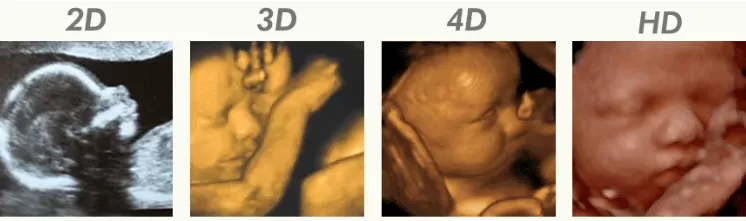

Adakah perlu untuk buat ultrasound scan sehingga 4D, 5D, 6D?

Tak cukup ke dengan basic ultrasound 2D yang nampak kuno tu?

Untuk ujian ni biasanya klinik hanya akan menggunakan scan 2D sahaja kerana pengukuran nya lebih tepat berbanding 3D.

Jadi bila boleh buat scan 3D, 4D, 5D, 6D tu?

Biasanya untuk mendapatkan image capture yang baik sehingga nampak wajah bayi, mommies perlu membuat scan ketika kandungan berumur lingkungan 28-34 minggu. Bergantung kepada kedudukan bayi dalam kandungan.